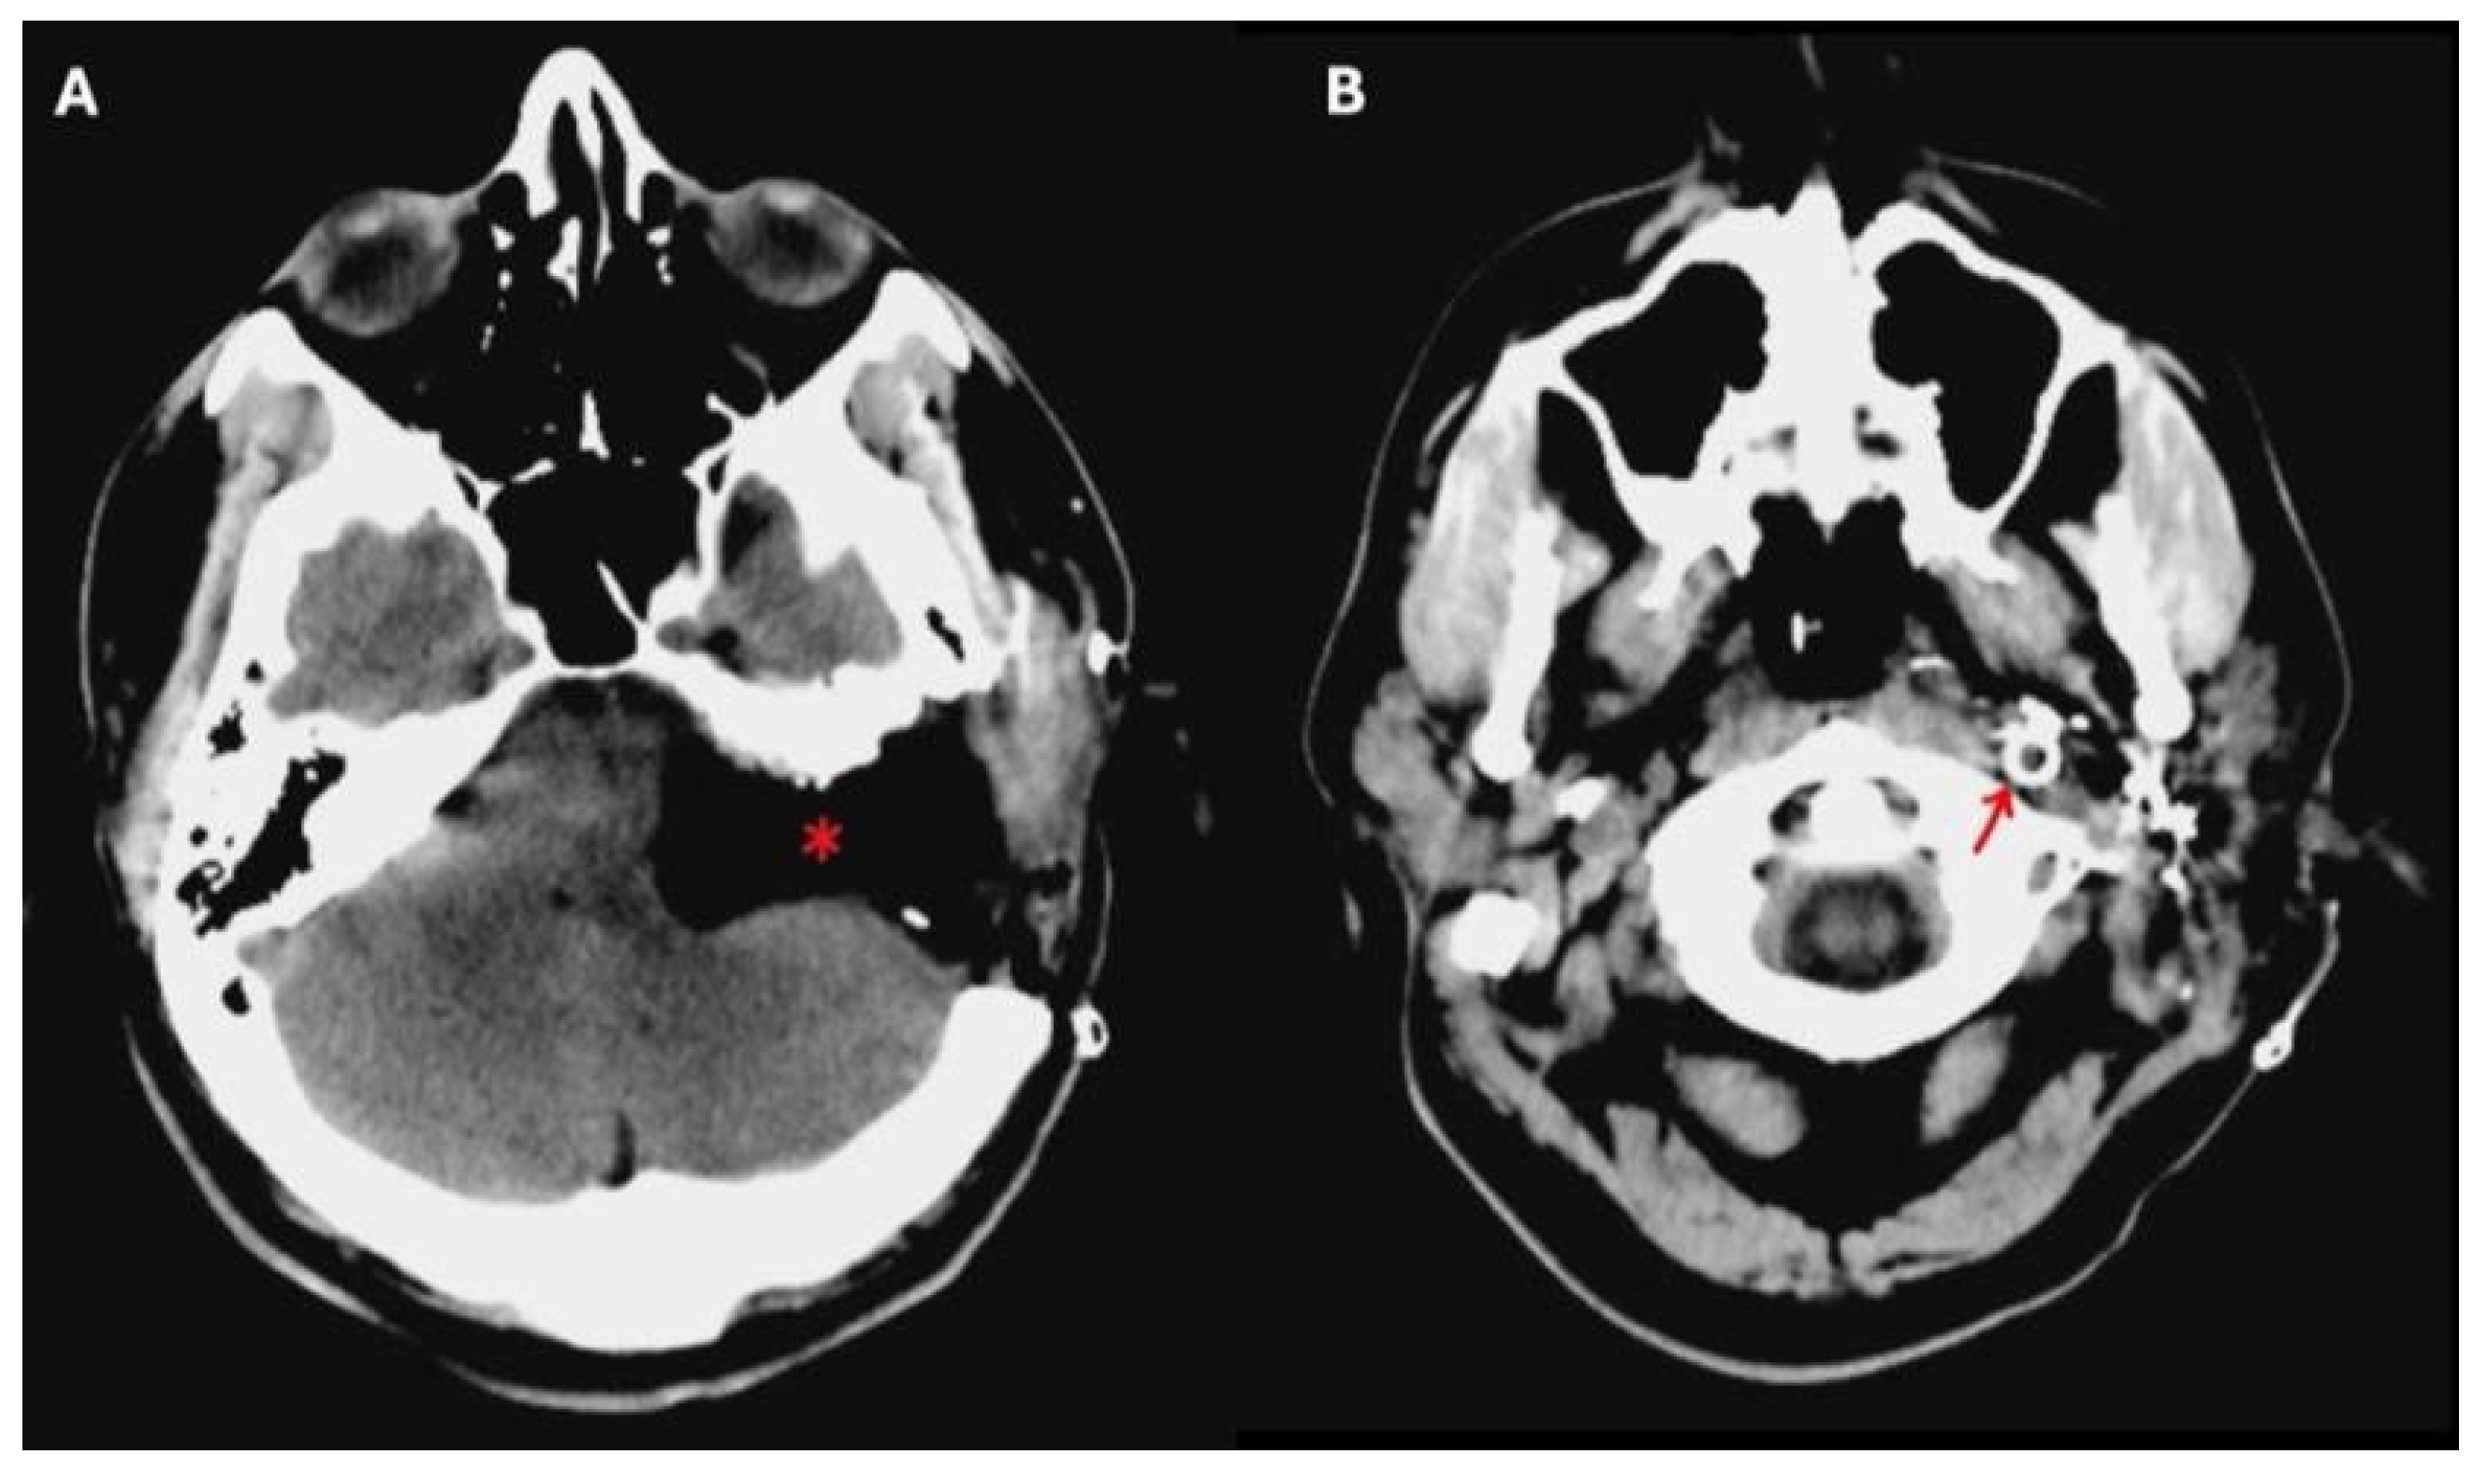

Figure 2. A postoperative brain CT scan after total removal of a TJ-PG Di2 in a single-stage procedure. In (A), * indicates the surgical cavity after the total removal of the TJ-PG Di2. In (B), the red arrow indicates the endovascular stent placed preoperatively in the internal carotid artery.

Preoperative angiography has played a vital role in allowing these kinds of large surgical resections, since it gives information concerning the vascularity of the tumor, and the involvement of the internal carotid artery (ICA) and the tumor-feeding vessels, also allowing for their selective embolization. Balloon occlusion testing can inform the risk of stroke should the ICA be sacrificed during the procedure, and an endovascular stent in a tumor-involved vertical petrous ICA can be placed for safer tumor dissection from the vessel walls (Figure 2) [6].

In our multicenter study, preoperative ICA stenting was performed in 8/32 patients, dependent on tumor classification. Additionally, permanent balloon occlusion of the intrapetrous ICA was carried out in two patients with Class C4-Di2 and Class C3-Di2 tumors, respectively. In the remaining 22 patients, no preoperative ICA intervention was performed. Notably, no intraoperative ICA wall injuries were observed in any of these patients, regardless of whether stenting or occlusion was performed. In particular, no statistically significant differences were observed between patients who underwent preoperative ICA stenting and those who underwent surgery without stenting, either in terms of intraoperative carotid artery rupture or the extent of tumor resection (total versus partial). Although several authors have recommended preoperative ICA stenting, there is currently no scientific evidence confirming the actual benefits of this procedure, especially when a partial resection is planned [10].